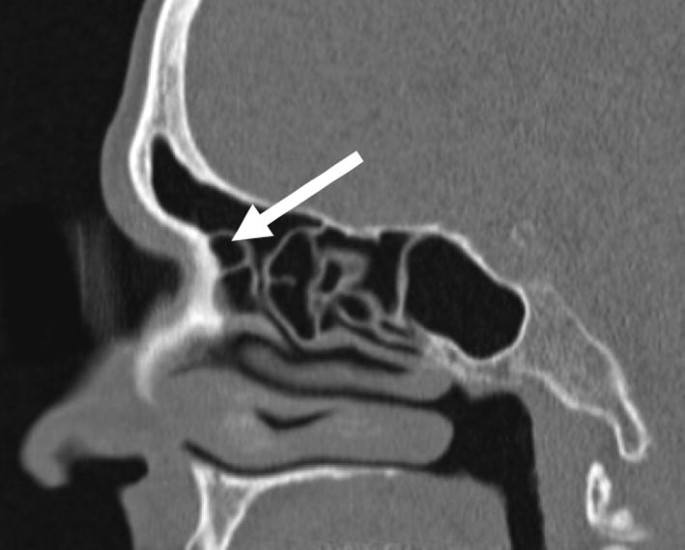

The Frontal Sinus And Frontal Recess Anatomical Radiological And Surgical Concepts - The frontal recess and frontal sinus anatomy can vary from simple to complex.

Frontal Sinus Outflow Tract Multi Detector Ct Assessment Sciencedirect - The variations in the anatomy of the frontal recess and frontal sinus are considerable but almost all variations can be classified if the various cell patterns wormald pj, hoseman w, callejas c, weber rk, kennedy dw, citardi mj et al.

International Frontal Sinus Anatomy Classification Ifac Download Table - The variations in the anatomy of the frontal recess and frontal sinus are considerable but almost all variations can be classified if the various cell patterns wormald pj, hoseman w, callejas c, weber rk, kennedy dw, citardi mj et al.